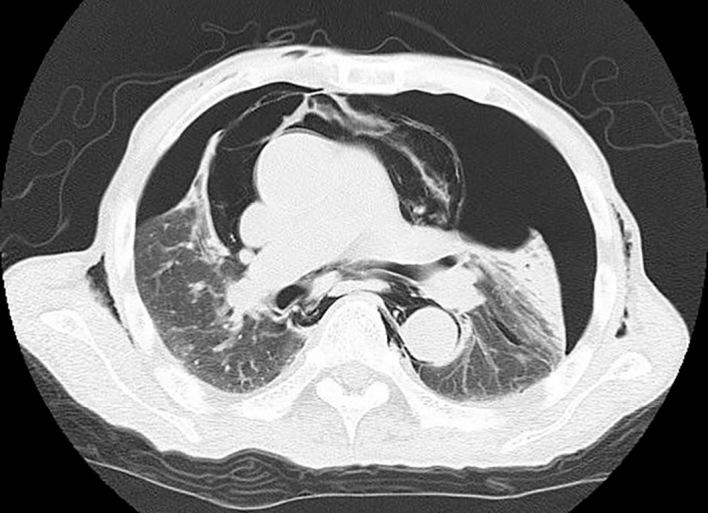

结果 患者的中位年龄为71岁(范围29 - 84岁)。内镜逆行胰胆管造影(ERCP)的适应证为恶性胆管梗阻24例,良性胆道疾病15例。技术成功率为78.6%(33/42),各穿刺途径间相似(p = 0.377)。总体并发症发生率为16.7%(7/42),各穿刺途径间相似(p = 0.489)。然而,2例经TE途径的EUS-RV患者发生了纵隔气肿。未发生与EUS-RV相关的死亡。